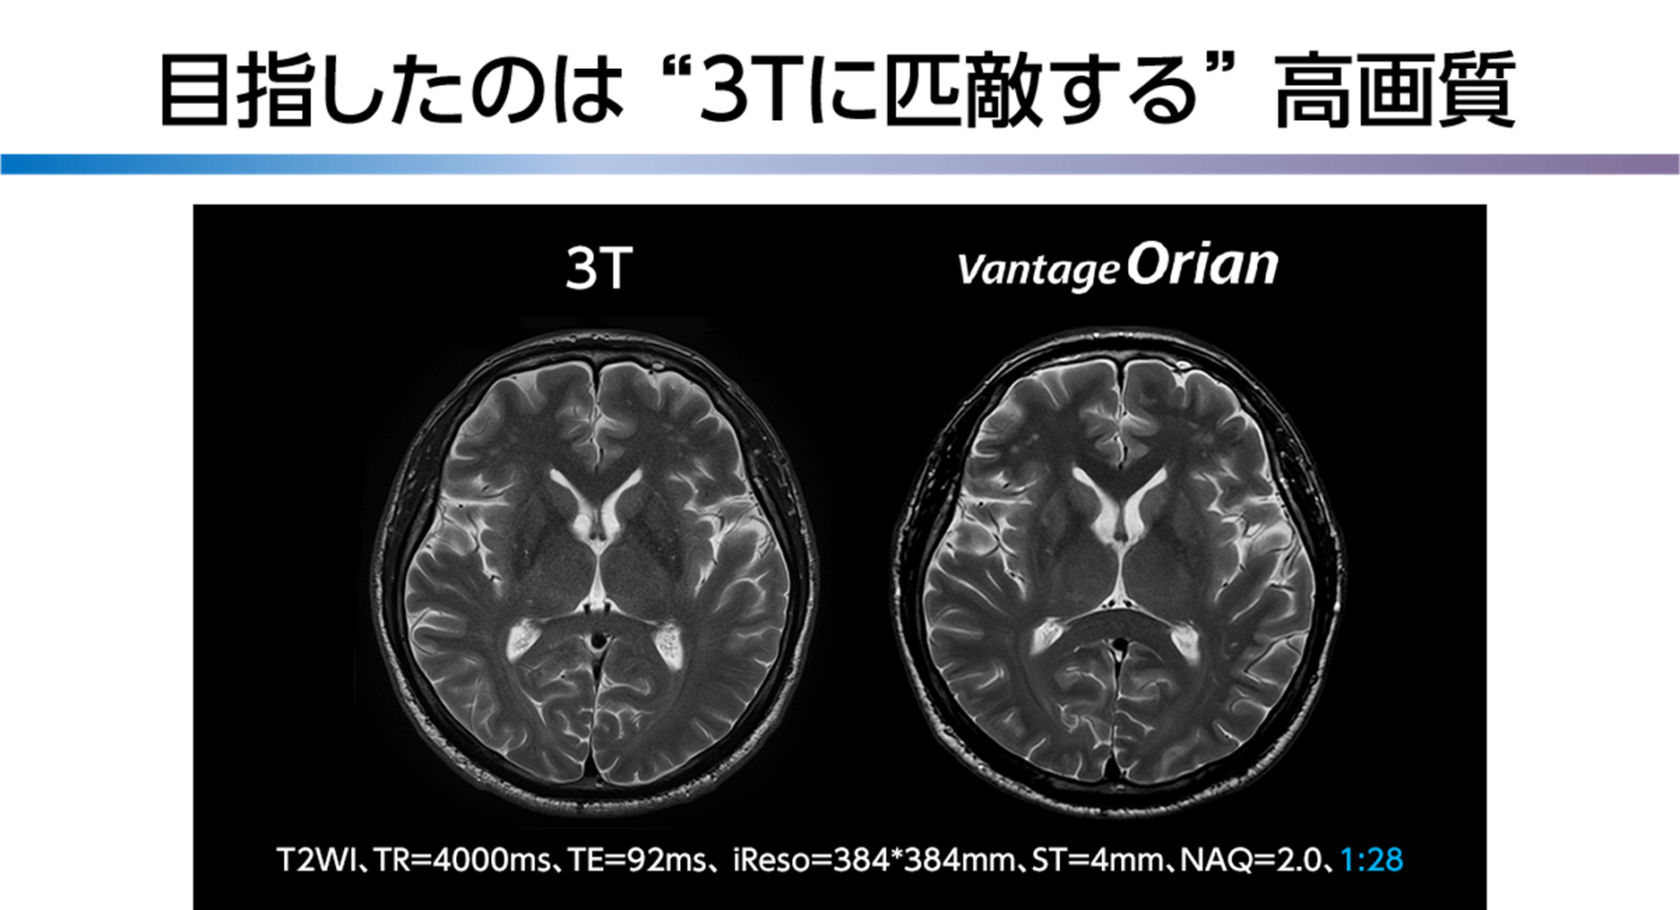

Vantage Orian là hệ thống chụp cộng hưởng từ 1.5 Tesla Open Bore 1.5 Tesla mang lại cả hiệu suất lâm sàng tiên tiến và lợi nhuận cao, đồng thời góp phần to lớn vào việc quản lý bệnh viện. Bằng cách kết hợp công nghệ cải tiến SNR được thiết kế bằng cách sử dụng công nghệ phần cứng và học sâu được phát triển với thiết bị 3-Tesla, chúng tôi nhắm đến hình ảnh chất lượng cao tương tự như hình ảnh của thiết bị 3-Tesla trong các cuộc kiểm tra lâm sàng.

Vantage Orian hướng đến chất lượng hình ảnh cao như 3 Tesla với công nghệ cải tiến SNR “Công cụ Clear-IQ thông minh tiên tiến (AiCE)” được thiết kế bằng cách sử dụng máy học sâu. Hơn nữa, bằng cách kết hợp các ứng dụng tốc độ cao như “NÉN TỐC ĐỘ”, chất lượng hình ảnh cao có thể đạt được mà không làm giảm tốc độ cao.